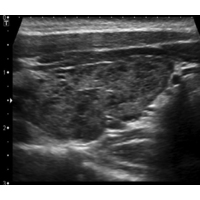

Die für die Hashimoto-Thyreoiditis typischen Antikörper im Blut sind die Antikörper gegen die thyreoidale Peroxidase (anti-TPO-AK) und die Antikörper gegen Thyreoglobulin (Tg-AK). Im Ultraschall stellt sich die Schilddrüse im Vergleich zum gesunden Gewebe dunkler (echoarm) dar.

Sonographisches Bild einer Hashimoto-Thyreoiditis.